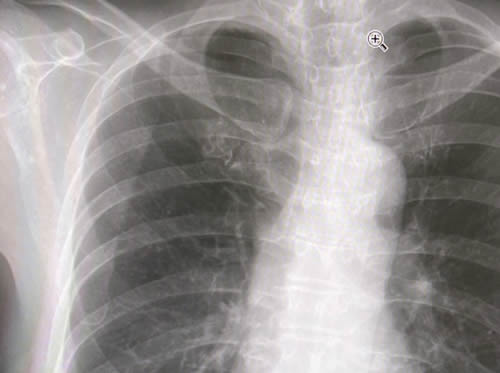

レントゲン画像を見て、医師が言う。

「背骨、曲がってますね。特に対処する必要はないけれど。。」

中学生の時の斜めがけの重いカバンのせい? まあいい、いま不都合はない。透かした骨の画像はきれいだなあ。先生のカーソル、じゃまだけど。